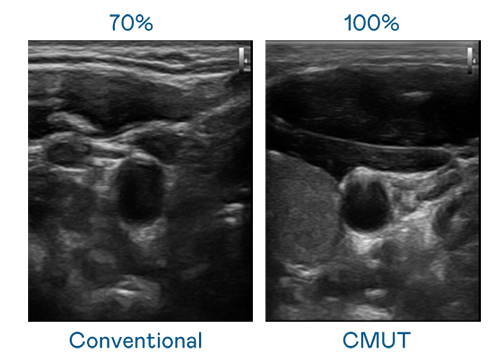

CMUT 技术是一种用电容式微机电元件来产生超音波讯号的技术。与传统 PZT 压电式技术相比,CMUT 频宽增加 30%,更宽频的超音波讯号让影像解析度大幅提升,是实现高影像品质医疗超音波扫描、促进精准医疗发展的关键技术。

大频宽带来超清晰影像

超音波影像的解析度高低,首先取决于探头能发出的讯号频宽。熊猫国际 CMUT 可提供高清晰的超音波讯号,提供高频宽、高灵敏度、影像纹理细节更高的超音波影像,协助医护人员缩短影像判读时间及利用精准的医疗影像进行诊断。